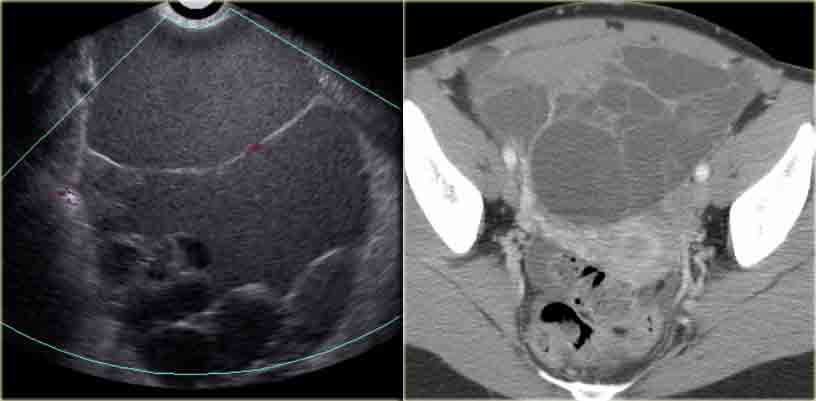

Комплексная геморрагическая киста яичника формируется при кровотечении из Граафова фолликула либо фолликулярной кисты. На УЗИ геморрагические кисты выглядят как однокамерные тонкостенные кистозные структуры с наличием тяжей фибрина или гипоэхогенных включений, с хорошей проницаемостью для ультразвука. На МРТ геморрагические кисты характеризуются высокой интенсивностью сигнала на Т1 FS сканах, при этом на Т2 ВИ дают гипоинтенсивный сигнал. При допплерографии внутренний кровоток отсутствует, компонент, накапливающий контраст, внутри кисты на КТ или МРТ не определяется. Стенка геморрагической кисты имеет вариабельную толщину, часто с наличием сосудов, расположенных циркулярно. Несмотря на то, что геморрагические кисты обычно проявляются острой болевой симптоматикой, они могут быть случайной находкой у пациентки, не предъявляющей никаких жалоб.

На сонограммах определяется геморрагическая киста со сгустком крови, имитирующим новообразование. Тем не менее, при допплерографии внутреннего кровотока в кисте не выявлено, а проницаемость ее для ультразвука не снижена.

На УЗИ в обоих яичниках определяется мягкотканный (солидный) компонент. Тем не менее, проницаемость для ультразвука с обеих сторон не нарушена, что позволяет предположить наличие геморрагических кист. При допплерографии (не представлена) кровоток в образованиях отсутствует.

Как отличить геморрагическую кисту на МРТ? В режиме Т1 в обоих образованиях определяется компонент с высокими сигнальными характеристиками (жир, кровь или жидкость, богатая белком). При жироподавлении интенсивность сигнала не уменьшается, что в целом позволяет исключить тератому, содержащую жировую ткань, и подтвердить наличие геморрагической жидкости.